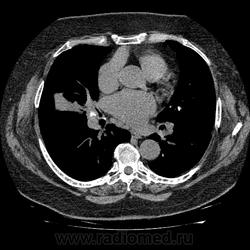

Женщина 72 года. Лечила пневмонию, сделала КТ. Ваши мнения, пожалуйста.

Ну м.б. и был тут туберкулез когда-то. М.б. я не прав, но плотность параплеврального уплотнения к "мясу"(40-50)

т.е. не жидкость. Прослеживаются на этом фоне бронхи. Т.е. ближе к фиброзу легочной ткани, чем к плевриту. Думаю поствоспалительный ( этиологию не спрашивайте) фиброз ( ну, иногда, как перисциссурит пишут, я не согласен с этим), узлы - с кальцинозом, обращаю внимание на центральное четкое кальцинирование, т.е. не острое и не онко.

Фиброз и точка.